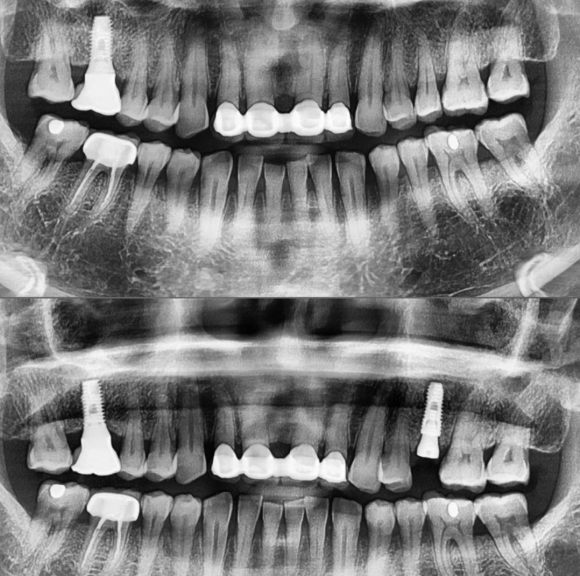

치아의 흔들림 그리고 극심한 통증으로 인한

발치 후 즉시 식립 임플란트 입니다.